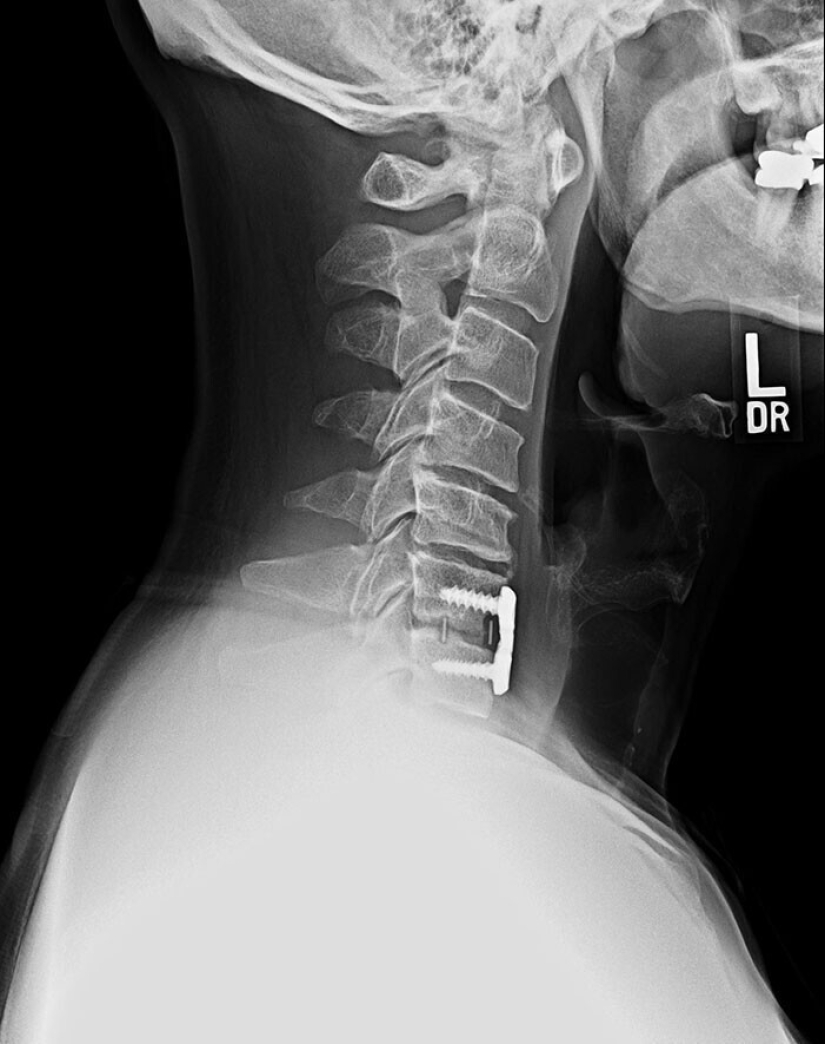

Contenedor nedorazumeniya ósea las células y las células madre, que se inserta en el cuello del paciente para la regeneración de la columna vertebral